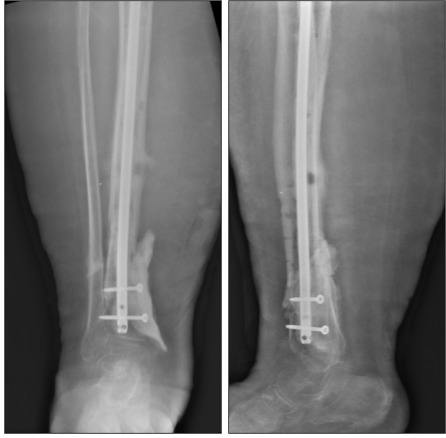

At thirty-three weeks, the patient presented to the emergency department with substantial right lower extremity pain and fevers. Subsequent radiographic imaging revealed he had broken one of the pins on his external fixator (figure 6). The external hardware was subsequently removed the next morning, giving the patient a hardware holiday while the definitive treatment was planned. MRI imaging revealed continued tibial nonunion and chronic osteomyelitis (Figure 7). Approximately one week later, the patient was taken for another I&D with excision of nonviable bone, placement of antibiotic coated tibial intramedullary nail, and placement of antibiotic cement spacer in the remaining tibial void measuring 7x3x3 cm (Figure 8). The patient was allowed partial weight bear postoperatively. Appropriate antibiotics were again determined from the intraoperative cultures by the infectious disease team, and at this time were positive for S. lugdenensis and S. agalactiae. He had made progress controlling his diabetes, as his most recent hemoglobin A1c was 4.5. Discussion with the patient was that this was a limb salvage procedure in an attempt to avoid amputation and that typically the cement spacer needs removal at a future date and replacement with bone graft.

At thirty-eight weeks, four weeks after the most recent surgery, the patient was reported that he was ambulating well in a walking boot and his pain was significantly improving. At this point there was a discussion about the appropriate next steps. The patient was informed that in most situations, the bone cement is removed and replaced with bone graft 1-2 months after placement. While the antibiotic cement spacer allows for slow elution of antibiotics, it is not traditionally intended to provide permanent structural support.

At forty-two weeks, eight weeks after the most recent surgery, the patient had felt his best since the initial trauma, reporting that he had no pain as he ambulates full weight bearing in a boot, and that his activity level had returned close to his normal baseline. At this time, the patient was not interested in any additional surgeries, and elected to postpone the second procedure with plans to exchange the cement for bone graft only if needed.